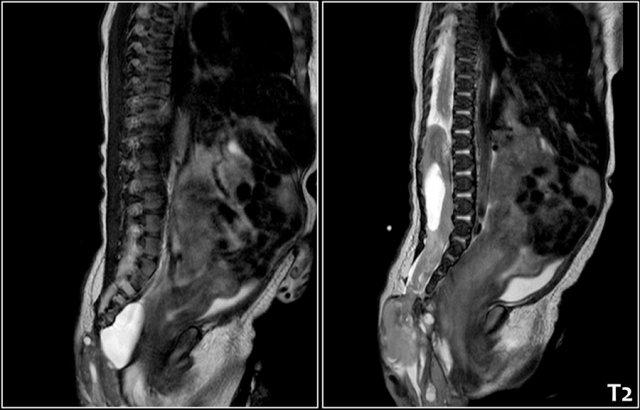

Sự xâm lấn vào ống sống có thể thấy được trên siêu âm, nhưng MRI cung cấp cái nhìn tổng quan tốt hơn và là tài liệu để so sánh trong tương lai.

Hình MRI cắt dọc cạnh đường giữa cho thấy một khối dạng nang trước xương cùng.

Bé gái sơ sinh với u quái vùng cùng cụt có thành phần đặc và dạng nang cả bên ngoài lẫn bên trong, kèm theo sự xâm lấn lớn vào ống sống.